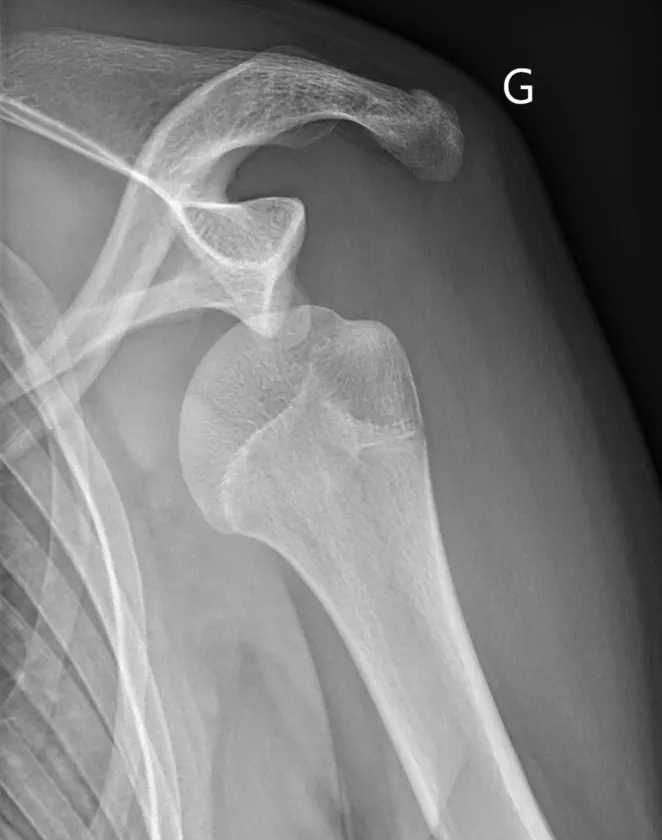

Dans un premier temps des radiographies permettent d'avoir une orientation diagnostique en corrélation avec l'examen clinique du chirurgien. Il s’agit du bilan de débrouillage qui sera complété le plus souvent par un arthro-scanner ou une IRM.